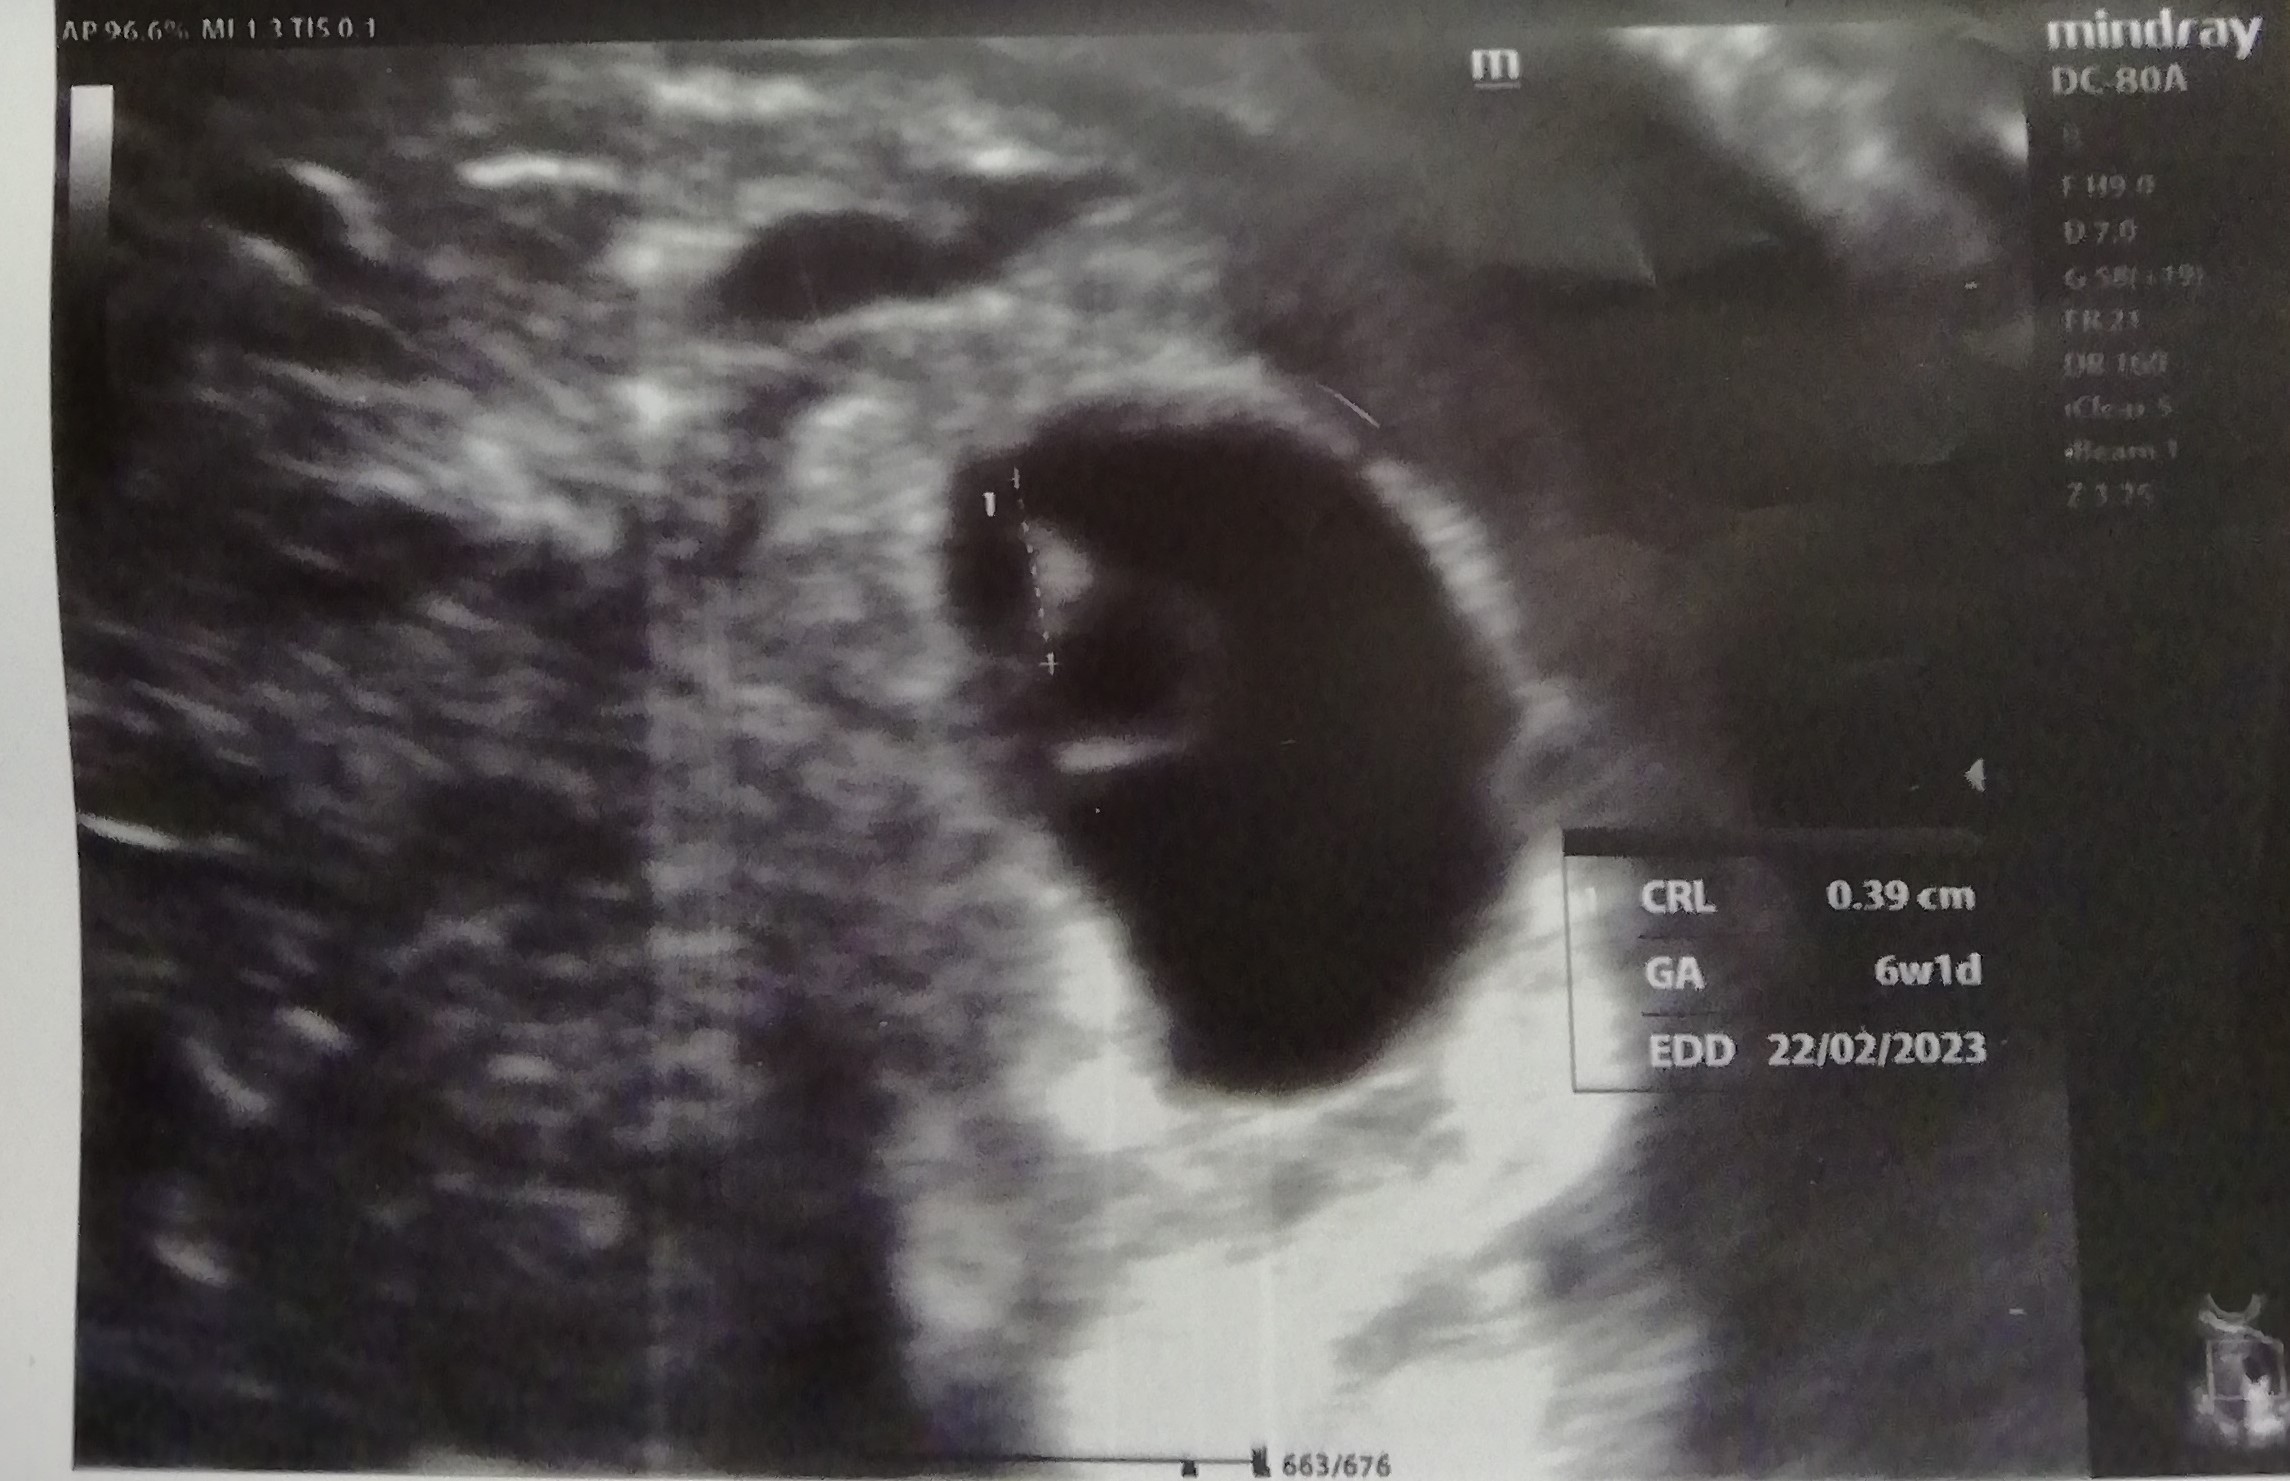

Seison ultraäänikuva kädessä keskellä ruuhkaista kaupunkia.

Laitan viestin Miehelle, koska tiedän hänen odottavan sitä. "Yksi, jonka sydän on alkanut kaksi päivää sitten lyödä, ja lyö edelleen", kirjoitan. "Ok", saan vastaukseksi.

Miten idioottimaista on seisoa täällä lelujen keskellä, viikolla 6+1?